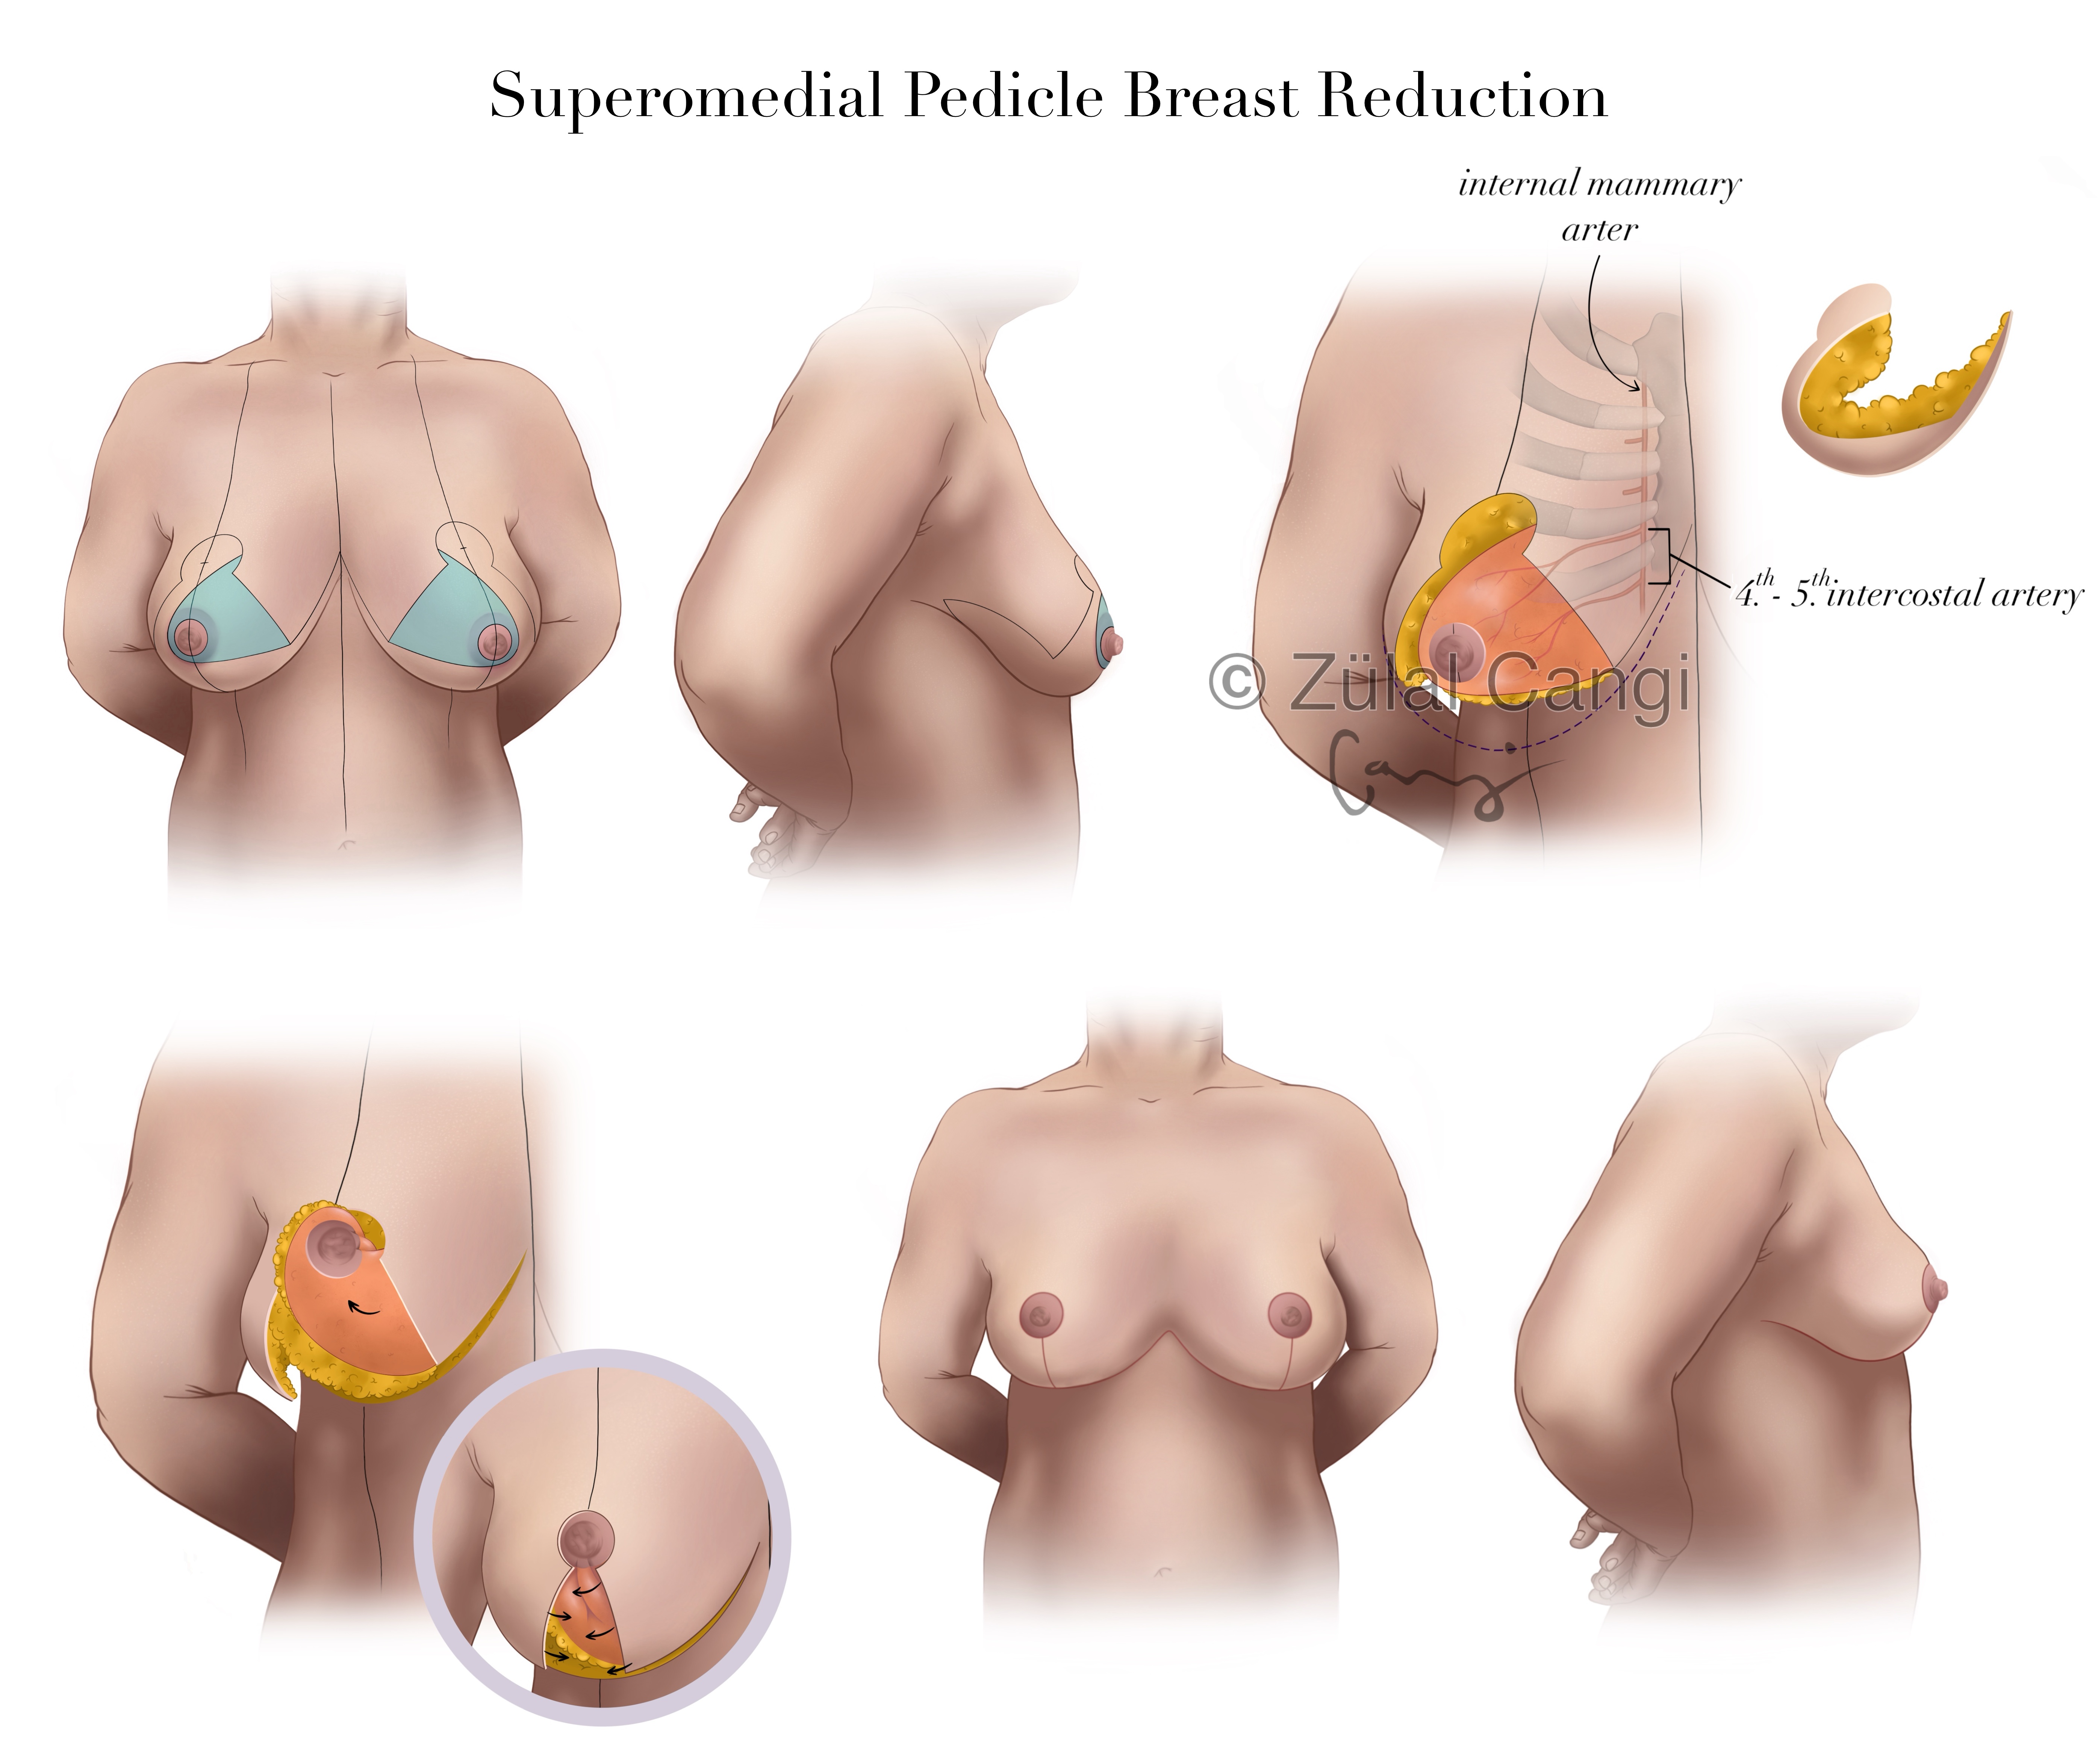

Sanatın estetiğini bilimin kesinliğiyle bir araya getiren Zülal Cangi, medikal ve bilimsel illüstrasyon alanındaki çalışmalarıyla akademik yayınlar, eğitim materyalleri ve çeşitli bilimsel platformlar için görsel içerikler üretmektedir. Amacı, bilimsel bilgiyi yalnızca doğru biçimde aktarmakla kalmayıp, aynı zamanda öğretici ve estetik bir dille görünür kılmaktır.

PORTFÖY